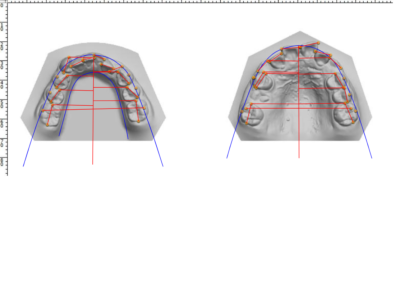

Many of us are not born with picture perfect teeth. For the straight teeth and alignment many people are searching for, braces is a common and effective treatment. Precision Dental Care uses the latest X-Ray technology to trace and model your teeth for your unique dental needs. From crooked teeth to alignment issues, braces can solve a variety of oral concerns.

Before and After Gallery